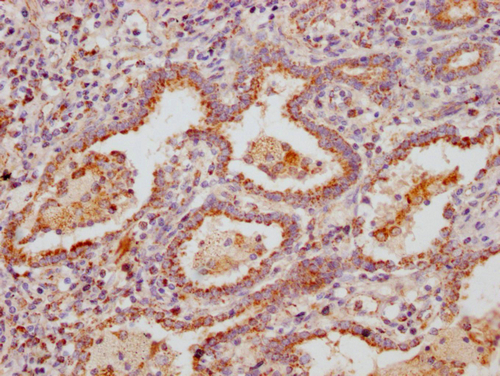

IHC image of CSB-PA875718LA01HU diluted at 1:300 and staining in paraffin-embedded human lung tissue performed on a Leica BondTM system. After dewaxing and hydration, antigen retrieval was mediated by high pressure in a citrate buffer (pH 6.0). Section was blocked with 10% normal goat serum 30min at RT. Then primary antibody (1% BSA) was incubated at 4°C overnight. The primary is detected by a Goat anti-rabbit polymer IgG labeled by HRP and visualized using 0.05% DAB.